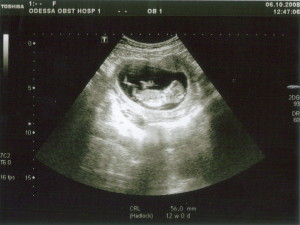

Знімки УЗД на 11 тижні вагітності

- УЗД - Якщо воно не було зроблено до 11 тижнів, необхідно виконати на 11 тижні. В ході дослідження лікар з'ясує, чи відповідає розвиток плода терміну вагітності, оцінить стан внутрішніх органів плоду і визначить місце прикріплення хоріону (майбутньої плаценти).